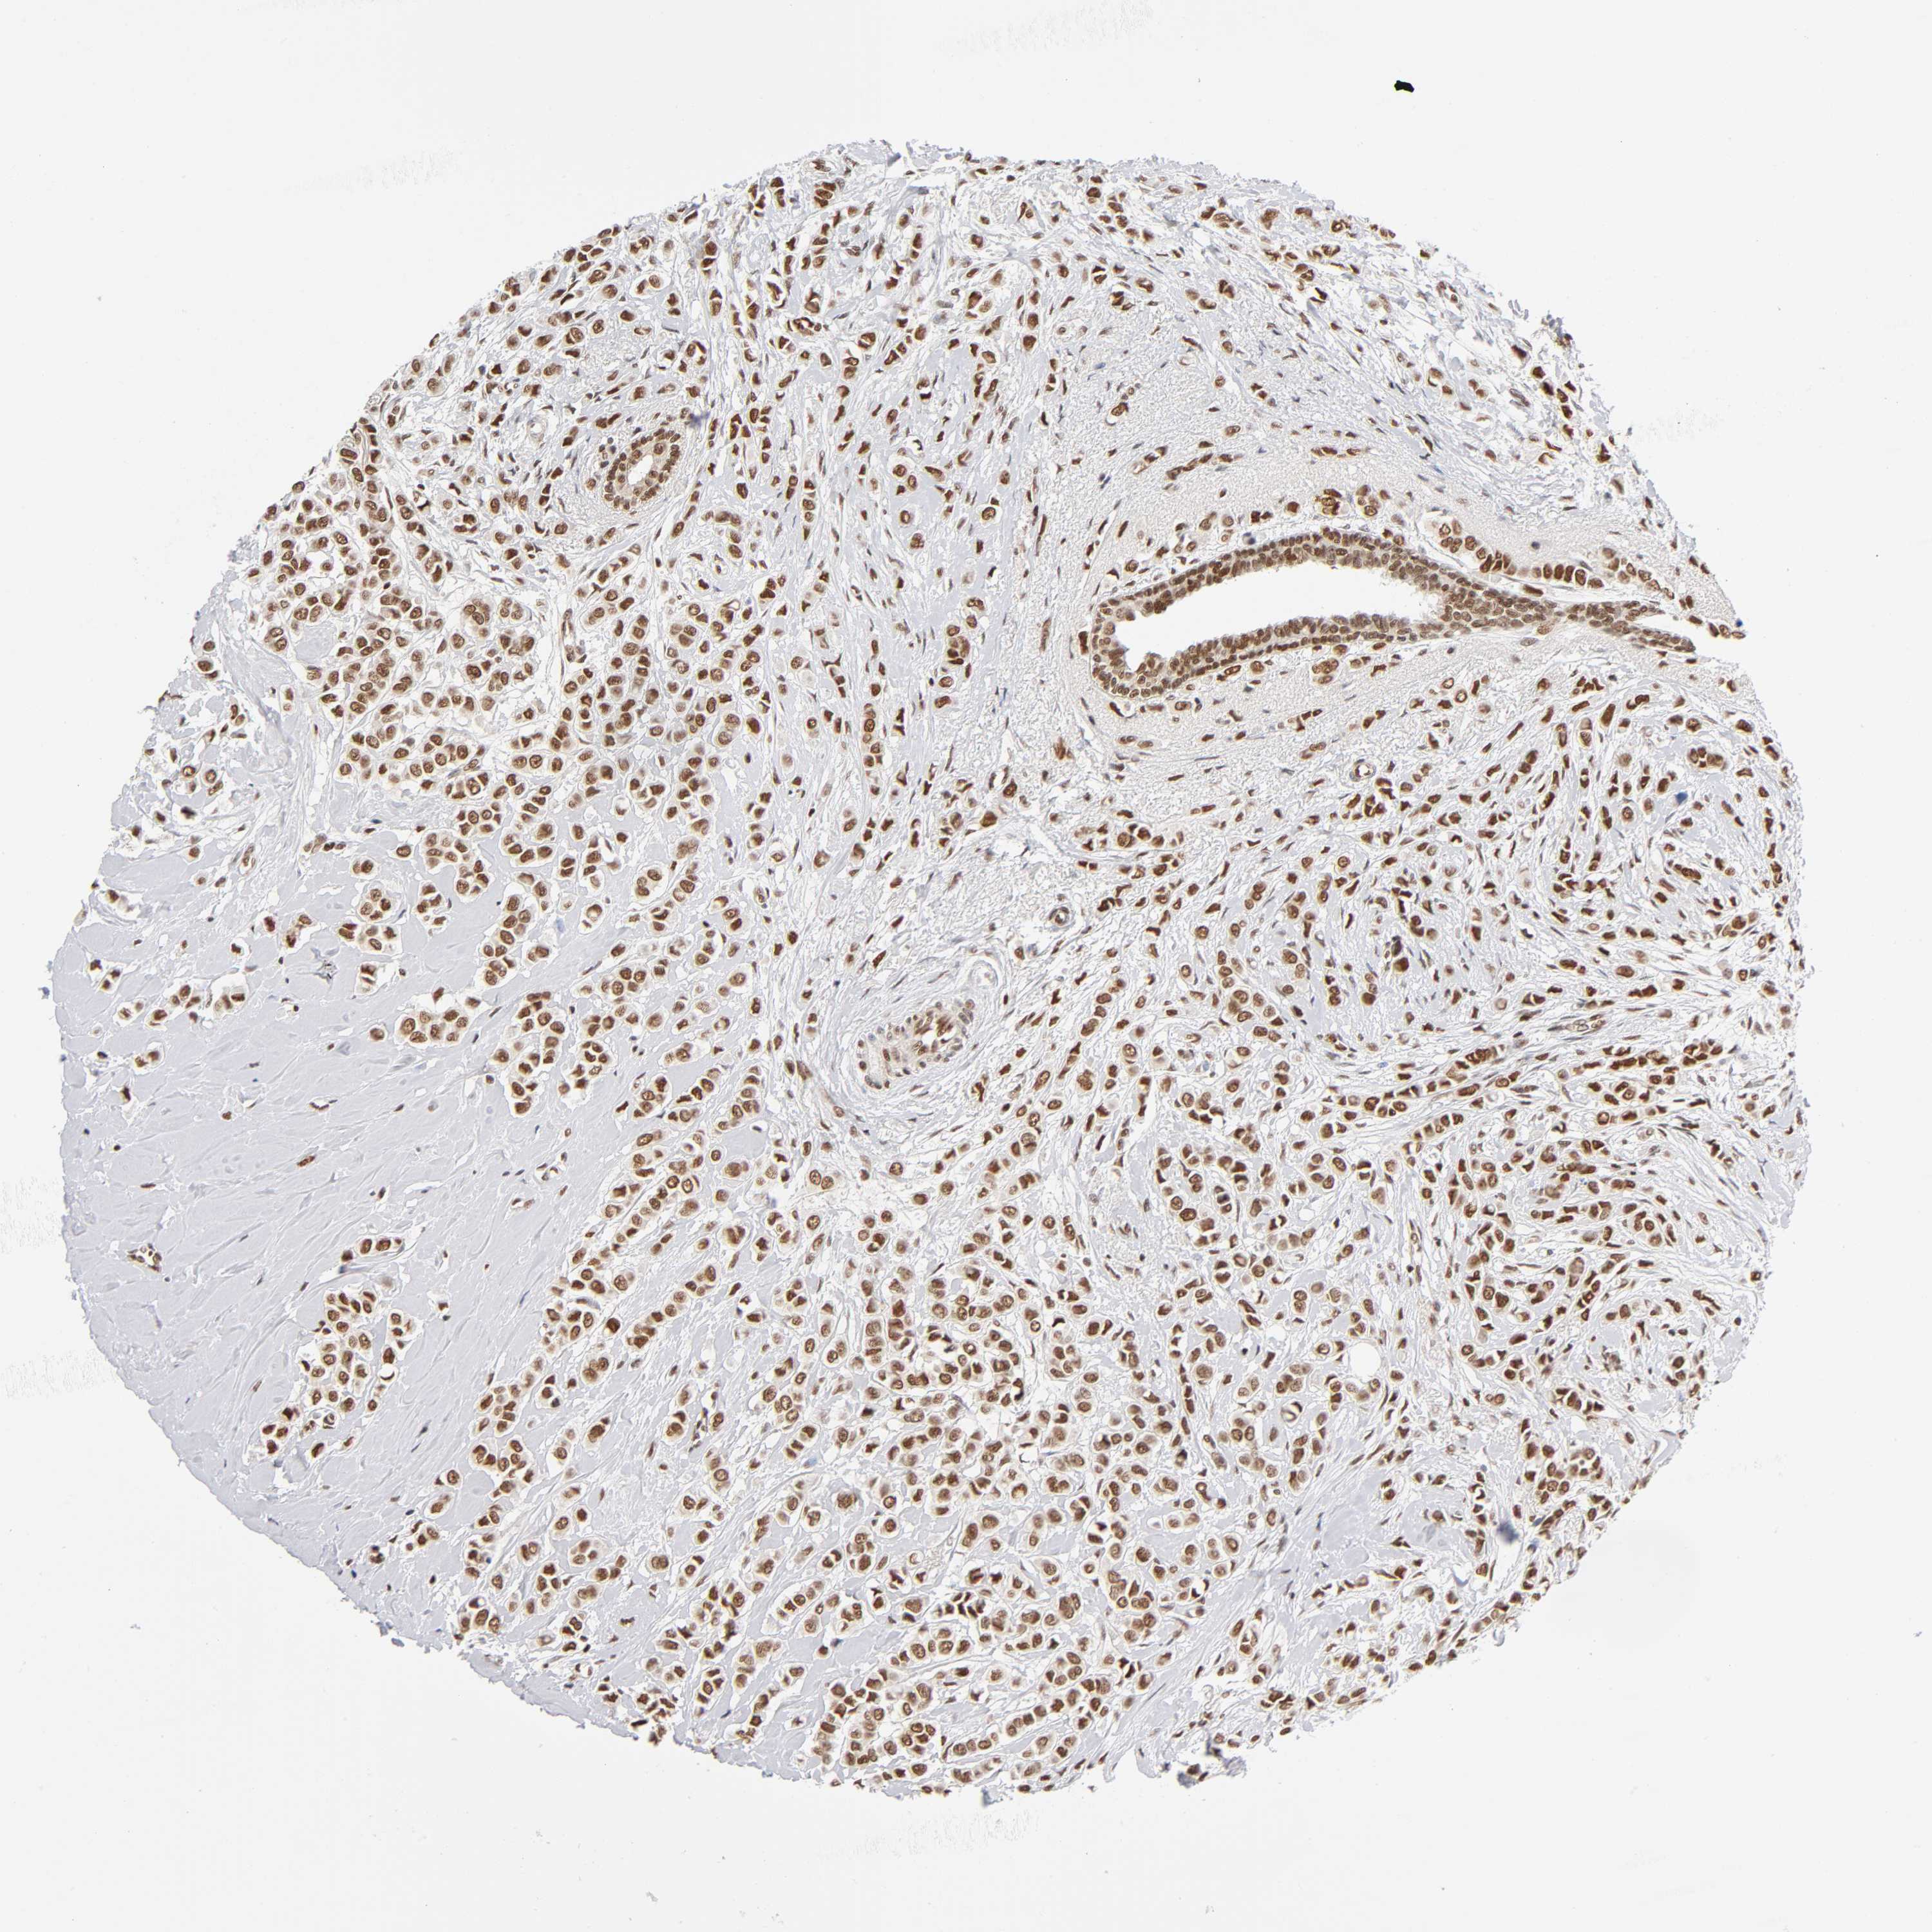

CANCER BREAST CANCER Show tissue menu

BRCA TCGA BRCA VALIDATION PROTEIN EXPRESSION